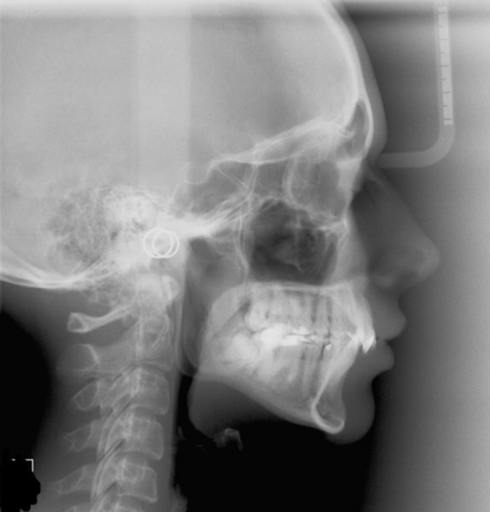

I have a bad underbite. When I was around 12 or 13 I had braces. At that time they asked if I would like to have surgery to fix my underbite and I said no because it never really bothered me. I'm almost 25 now and I'm starting to have pain in my jaw. Some days it feels as if I can't relax it and it feels really tight. I also get headaches a lot and the pain goes from my jaw all the way to my head. If I wanted to get surgery would I have to get braces again since I have already had them? Can you get headaches from your jaw being out of line?